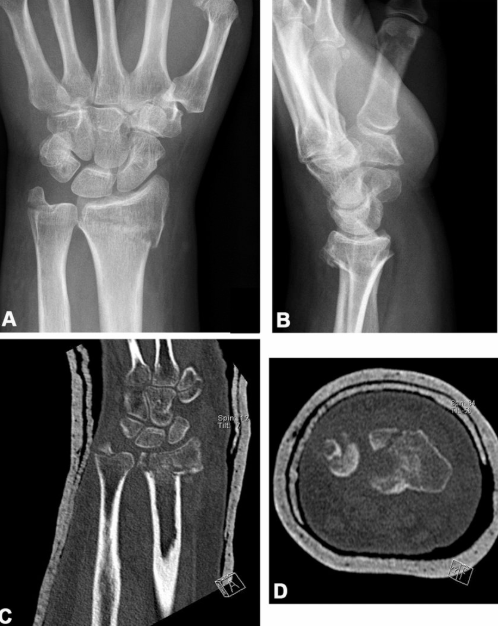

A Colles’ fracture is one of the most common types of wrist fractures, especially among older adults. It typically occurs when a person falls on an outstretched hand, causing the distal radius (the larger forearm bone) to break near the wrist joint.

It involves a fracture of the distal radius with the broken fragment angling upward (dorsally).

Often described as a “dinner fork” deformity due to the shape the wrist takes after the injury.

X-ray is the gold standard to confirm the fracture and evaluate displacement.

In complex cases, a CT scan may be recommended.